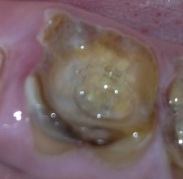

①虫歯があります

-

②虫歯を削り型取りします

③インレーを入れます

治療前:大きな虫歯です